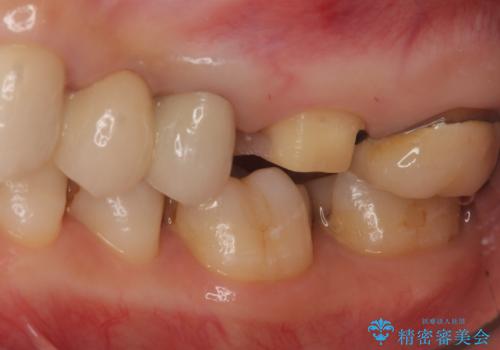

- 左上6 仮歯+フルジルコニアクラウン 11000円+77000円費用は治療当時の料金となります

向かい合わせの歯の咬みこみが強くインレーよりも強度の高いクラウンでの治療となりました。その中でも色が白くある程度の薄さでも耐久性を発揮するフルジルコニアクラウンでの修復を行いました。適合も良く色調もとてもなじんだため大変喜んでいただけました。